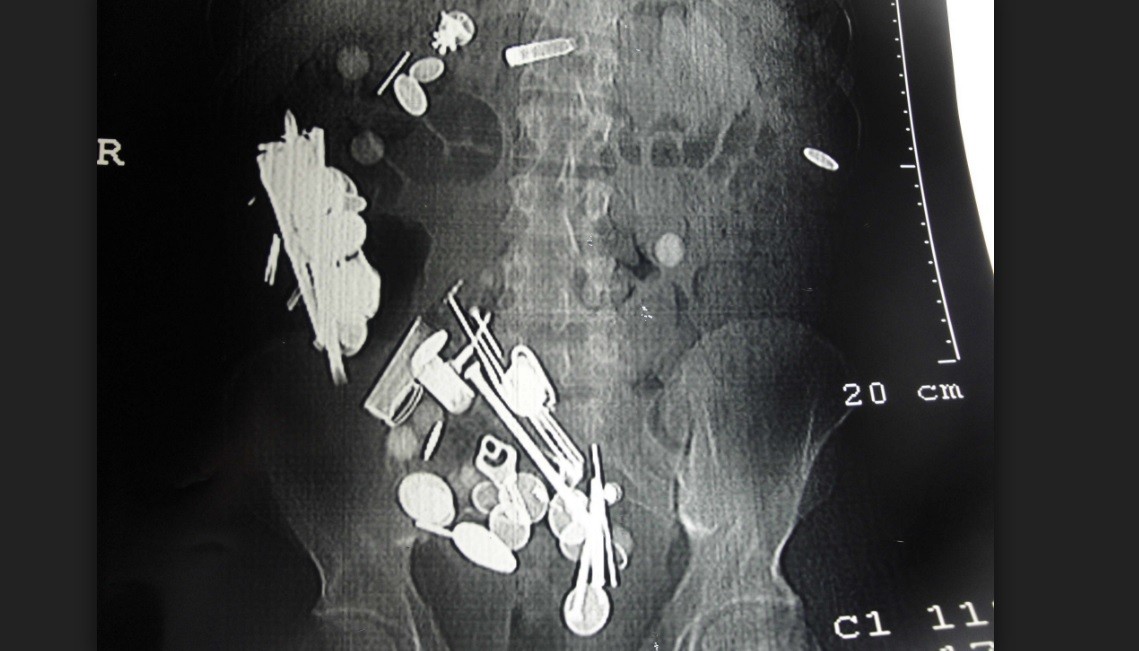

El hombre, de 32 años, acudió al hospital con un fuerte dolor en el estómago y, tras realizarle una radiografía, los médicos descubrieron todo lo que tenía en su interior. Los cirujanos del centro consiguieron extraerle todos estos metales.

Los cirujanos de un hospital de la India lograron extraer las 263 monedas, 150 clavos y una correa de acero para perros del estómago de un hombre. Según detallan los médicos, el hombre, de 32 años, desarrolló el hábito de tragar metales durante un proceso de depresión.

Según publica The Times of India, el hombre comenzó a tener un dolor agonizante en el estómago. Sus padres vieron hinchado su abdomen y decidieron llevarlo al Sanjay Gandhi Medical College & Hospital, en Rewa. Allí le hicieron una radiografía y descubrieron todo lo que tenía en su interior.